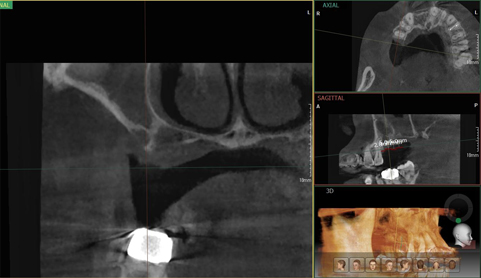

3D CT/파노라마 촬영을 통한 정확한 진단

단순한 치료라도 3D-CT/파노라마을 통해서 체크!

3D CT/파노라마

디지털 시뮬레이션을 통한 정확한 식립 위치와 깊이 진단.